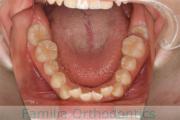

上顎

下顎

前歯の関係など

右側

正面

左側